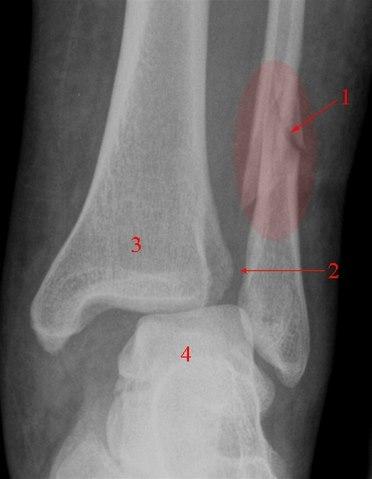

Brudd (1) gjennom distale fibula med ruptur av syndesmosen (2). Betydelig sprik i ankelgaffelen